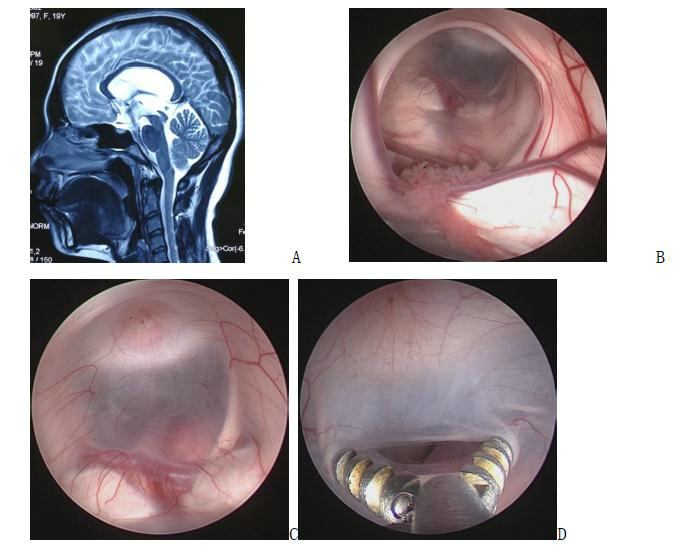

图5. A手术前磁共振图像;B 手术中截图,内镜下可见室间孔周围结构;C、D 三脑室底部及造瘘(瘘口下方可见基底动脉)